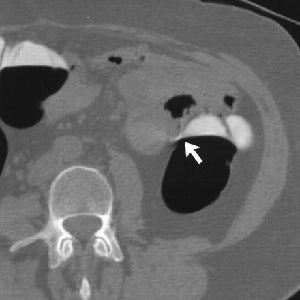

| Electronic cleansing artifact seen on 3-D virtual colonoscopy resulting from suboptimal fluid opacification in a 62-year-old man undergoing screening. Cleansed (left) and uncleansed (arrows, right) axial images show 2-D correlate of cleansing artifact, with jagged appearance at air-fluid level on subtracted image. (Images and caption used with permission of the American Roentgen Ray Society from AJR, © September 2003, Vol. 181:3, pp. 799-805.) |

Polypoid artifacts related to partial-volume effects are a more serious shortcoming of the primary 3-D read, according to the group. Such artifacts tend to occur where air-fluid levels interface with the colon wall, especially when a meniscus effect is also present, the group wrote. Air-fluid haustral-fold interfaces are another characteristic location of polypoid artifacts, making evaluation of the uncleansed 2-D images vital for accurate interpretation. Since these artifacts result from the cleansing process, they are often present on the electronically cleansed 2-D images as well.